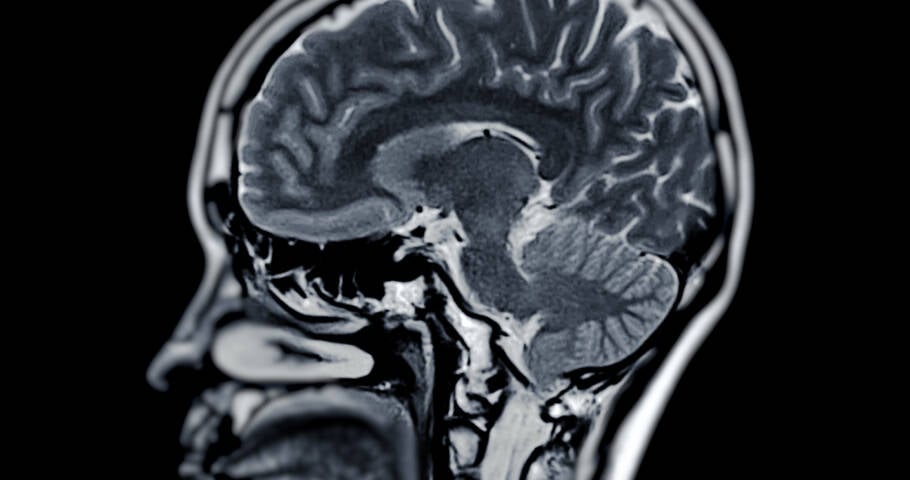

O hábito simples que melhora a saúde do seu cérebro, segundo estudo

Manter o cérebro afiado à medida que envelhecemos é uma preocupação crescente, e a ciência acaba de reforçar um caminho acessível e eficaz para isso: o exercício físico. Um estudo publicado no British Journal of Sports Medicine mostrou que uma rotina regular de atividades físicas pode melhorar significativamente a saúde cerebral em apenas 12 semanas […]

Manter o cérebro afiado à medida que envelhecemos é uma preocupação crescente, e a ciência acaba de reforçar um caminho acessível e eficaz para isso: o exercício físico. Um estudo publicado no British Journal of Sports Medicine mostrou que uma rotina regular de atividades físicas pode melhorar significativamente a saúde cerebral em apenas 12 semanas — com benefícios observados em todas as idades.

A pesquisa analisou 133 revisões de ensaios clínicos randomizados para entender como os exercícios afetam a cognição, memória e função executiva. Os resultados revelaram que a prática regular de exercícios promove um aumento perceptível na cognição, além de ganhos moderados em memória e na capacidade de planejar e organizar pensamentos. Crianças e adolescentes, em especial, apresentaram os maiores avanços na memória.

Como o exercício fortalece o cérebro

De acordo com o pesquisador Ben Singh, Ph.D., da Universidade do Sul da Austrália, o exercício físico estimula o fluxo sanguíneo e a oxigenação do cérebro, melhora a nutrição cerebral e estimula a liberação do fator neurotrófico derivado do cérebro (BDNF). Esse fator é essencial para o crescimento de novos neurônios e para o fortalecimento das conexões existentes entre as células nervosas.

Além disso, a atividade física reduz a inflamação e o estresse oxidativo, dois vilões ligados ao declínio cognitivo e ao envelhecimento cerebral. Também promove o equilíbrio de neurotransmissores como dopamina, serotonina e norepinefrina, que regulam o humor, o aprendizado e a memória. “A atividade física ajuda a regular os hormônios do estresse, como o cortisol, protegendo o cérebro dos efeitos negativos do estresse crônico”, explica Singh.

Outro fator importante é a melhora da função vascular. Quando os vasos sanguíneos estão saudáveis, o cérebro recebe mais oxigênio e nutrientes. Isso é fundamental para preservar a função cerebral, especialmente com o avanço da idade.